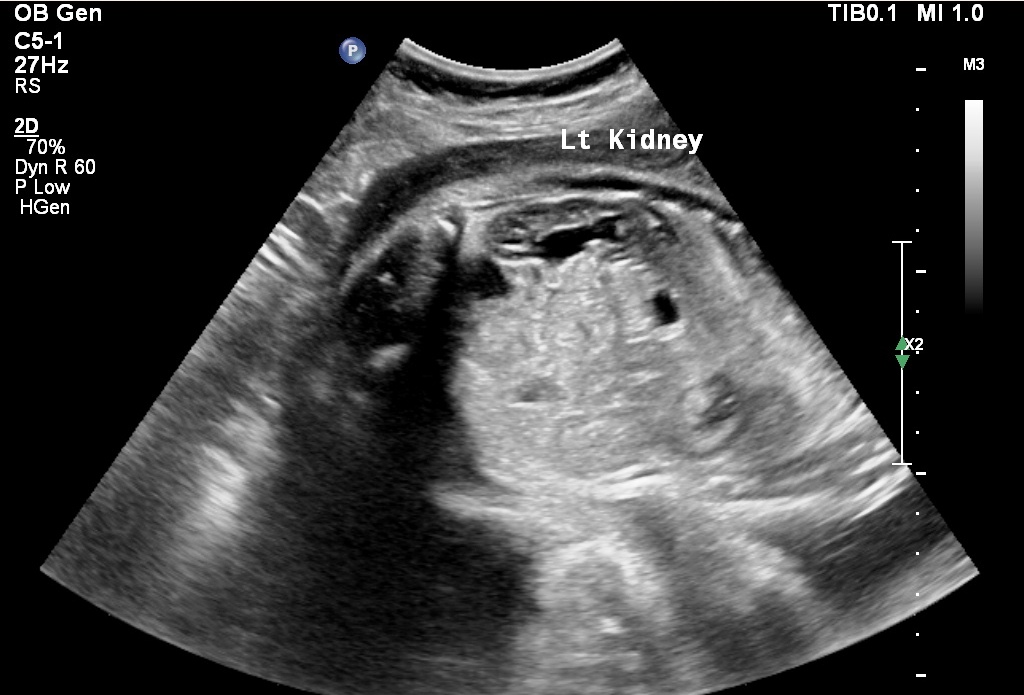

During the First Trimster Screening (Nuchal translucency, Nasal bone, etc)(11-13 weeks), the Anomalies Scan / Targetted Scan (20-24 weeks) we routinely examine the fetal heart and connecting blood vessels.